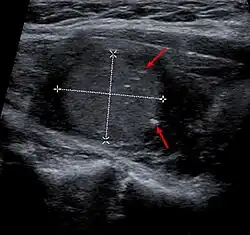

Las técnicas de diagnóstico, como la ecografía de alta resolución y la punción-aspiración con aguja fina (PAAF) permiten un diagnóstico precoz.[2] La ecografía evidencia mala delimitación del nódulo, por lo general de forma irregular por hipoecogeneidad, ausencia de halo de seguridad, calcificaciones, crecimiento comparado con exploraciones previas y vascularización intranodular. La PAAF es la prueba decisiva en el diagnóstico de cáncer tiroideo. La biopsia de tiroides muestra células de cáncer anaplásico, folicular, medular o papilar. Tanto la gammagrafía de tiroides que muestra un nódulo frío (es decir, que no se ilumina durante el examen) como la laringoscopia que muestra cuerdas vocales paralizadas suelen indicar cáncer de tiroides; otro tanto puede decirse de las concentraciones elevadas de calcitonina en suero (indicadoras de cáncer medular) o de tiroglobulina (que indican cáncer papilar o folicular, y también la presencia de cáncer residual).[2]